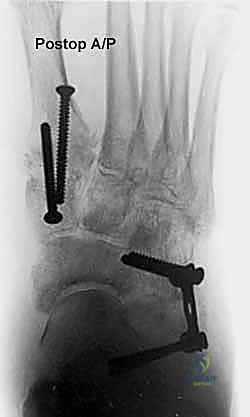

إطالة العمود الجانبي للقدم، أو قطع عظم إيفانز، هو إجراء جراحي حيوي لتصحيح تشوه القدم المسطحة المكتسبة الناتج عن قصور الوتر الظنبوبي الخلفي. يهدف إلى استعادة قوس القدم وتخفيف الألم وتحسين وظيفة القدم، ويتم على يد خبراء مثل الأستاذ الدكتور محمد هطيف.

في هذا الدليل المرجعي، سنسلط الضوء بشكل مكثف على الحل الجراحي المتقدم والفعال المعروف باسم إطالة العمود الجانبي للقدم (Lateral Column Lengthening)، وتحديداً التقنية الجراحية الدقيقة المسماة "قطع عظم إيفانز" (Evans Osteotomy). يُعد هذا الإجراء حجر الزاوية في استعادة الميكانيكا الحيوية الطبيعية للقدم، وإعادة بناء القوس المنهار، وتخفيف الألم بشكل دائم.

* الأشعة السينية (X-rays) مع تحمل الوزن: ضرورية لتقييم درجة انهيار القوس وزوايا العظام (مثل زاوية تالونافيكولار Meary's Angle).